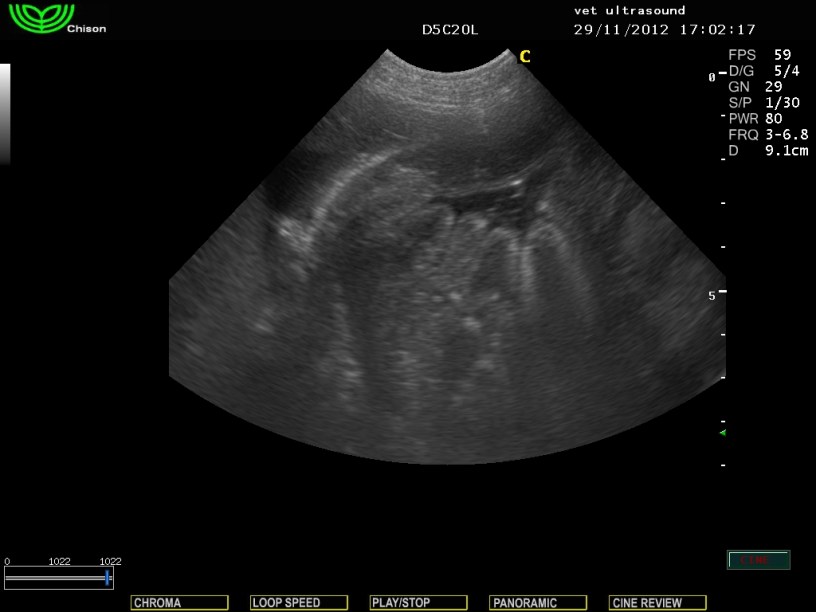

Στην υπερηχοτομογραφική εξέταση της κοιλίας βρέθηκε αύξηση της ηχογένειας της φλοιώδους μοίρας των νεφρών.

(ίδια ηχογένεια με το παρέγχυμα του σπλήνα)

Μικρή παρουσία ασκιτικού υγρού

(πιθανόν λόγω της απώλειας πρωτεινών)